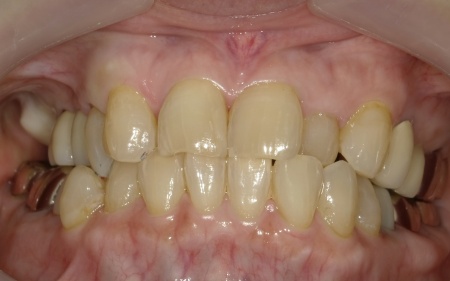

最後に、完成した人工歯を装着し、見た目や噛み合わせに問題がないことを確認して、治療を終了しています。